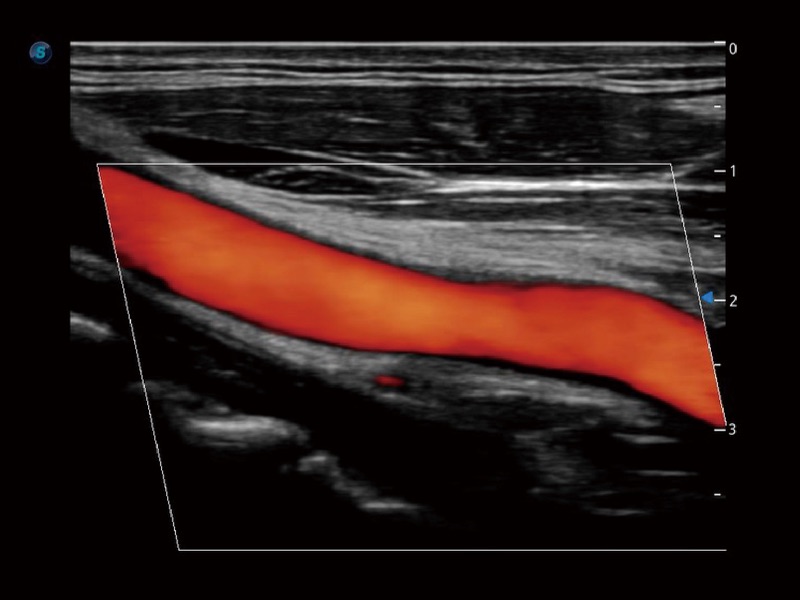

小器官应用

血管内中膜的厚度值是预测心血管疾病风险的重要指标,Auto IMT可以实现血管近场和远场内中膜厚度的自动测量,为临床提供快捷有效的诊断工具。

高分辨率血流成像技术提高了对低速血流信号的检测能力。在提高空间分辨率的同时,也克服了血流外溢现象,为用户提供更加真实的血流动力学信息。